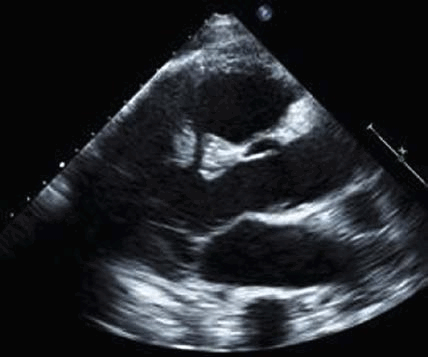

- Получите стандартный вид парастернальной продольной оси, показывающий митральный клапан. Оцените нормально ли встречаются кончики створок митрального клапана (т. е. касаются друг друга чуть ниже фиброзного кольца)? Или кончик одной створки пролабирует или свободно движется и возвращается в левое предсердие в систолу?

- Повторите двумерное (2D) изображение и цветное допплеровское сканирование митрального клапана в апикальном четырехкамерном и апикальном трехкамерном срезе. По техническим причинам низкое качество изображения нередко препятствует абсолютному определению того, есть ли молотящая створка МК, но есть эксцентрическая струя значимой МР или хордальная структура, колеблющаяся в левом предсердии проксимальнее митрального клапана, что повышает вероятность разрыва митрального аппарата.

Область митрального клапана на эхокардиографии может быть хорошо исследована. Был использован ряд методов оценки стеноза с разной точностью.

- Планиметрический метод: он включает отслеживание внутренней границы отверстия митрального клапана в диастолу. Было показано, что эти данные хорошо коррелируют с площадью клапана, измеренной при катетеризации. Он имеет свои ограничения, особенно при наличии значительной кальцификации кончика створки, плохого определения границ и различной степени времени открытия из-за фибрилляции предсердий.